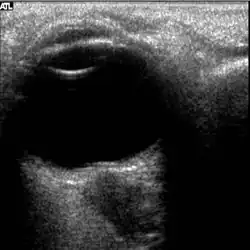

Figure 5: On-orbit ultrasound of posterior orbit of the fourth case of visual changes from long-duration spaceflight. In-flight ultrasound image of the right eye showing posterior globe flattening and a raised optic disc consistent with optic-disc edema and raised ICP.

Figure 6: On-orbit ultrasound of optic nerves of the fourth case of visual changes from long-duration spaceflight. In-flight ultrasound shows proximal kinking and increased optic nerve sheath diameter (ONSD) of approximately 12 mm that is consistent with raised ICPs. Optic nerve shown in purple and the ONSD in green.